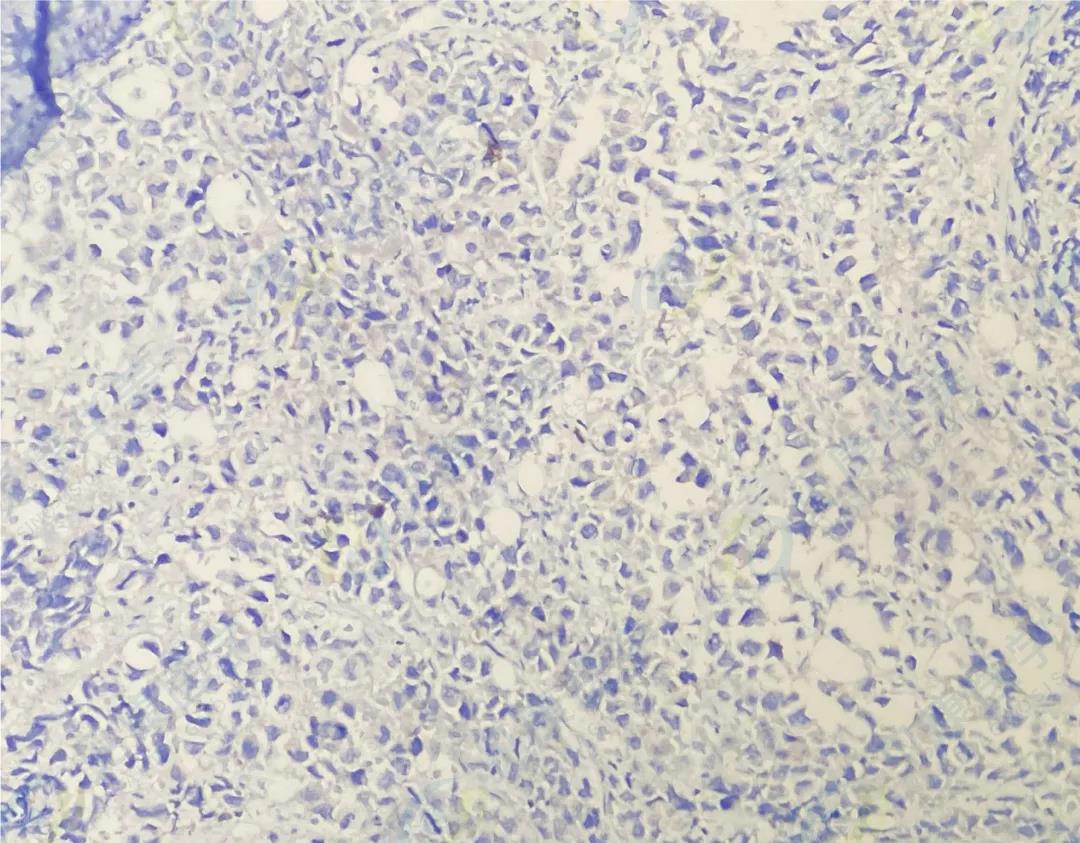

CD138

CD38

κ

λ